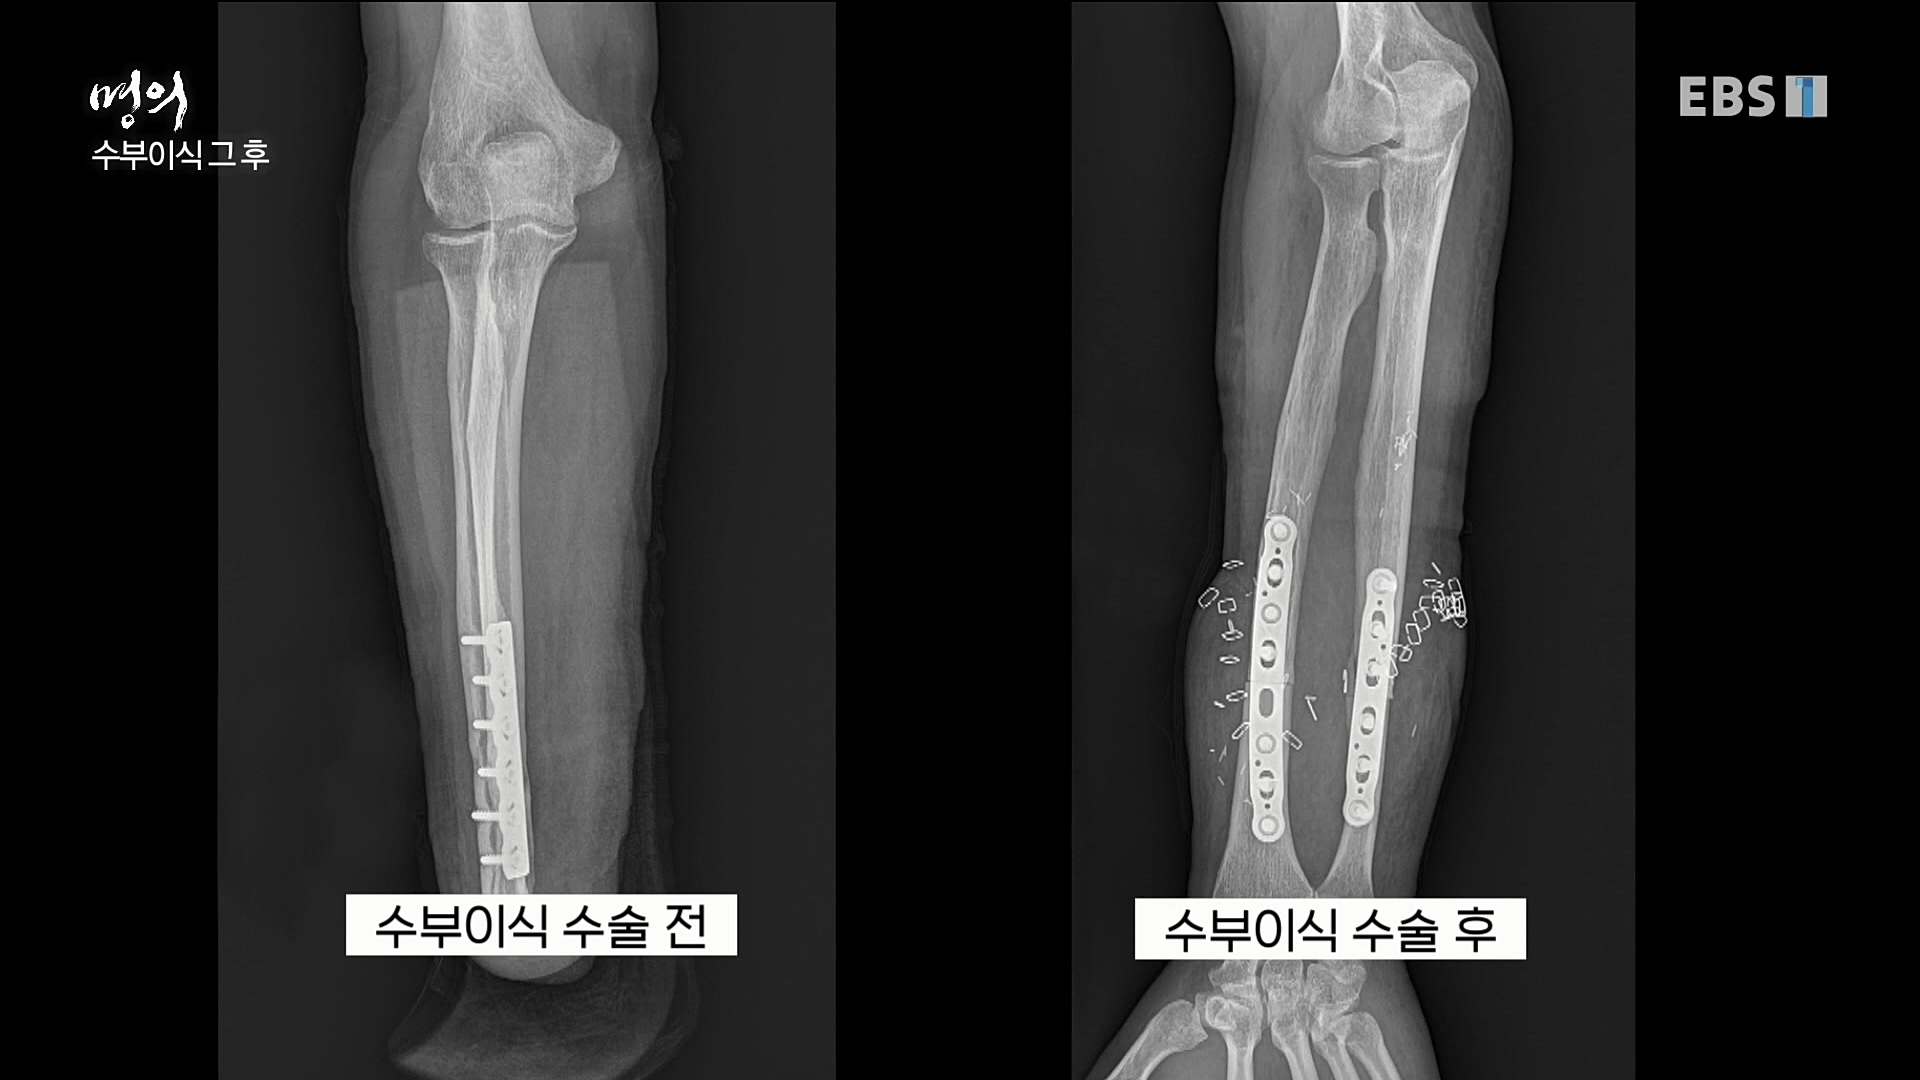

명의' 최윤락 교수와 함께 손목터널증후군, 드퀘르벵병, 팔꿈치터널증후군, 흉곽출구증후군, 손목 물혹(결절종), 방아쇠수지 등 손과 팔에 생길 수...

이날 EBS 명의 '손이 보내는 경고, 저림과 통증' 편에서는 정형외과 전문의이자 수부외과 세부전문의 최윤락 교수와 함께 손과 팔에 생길 수 있는...